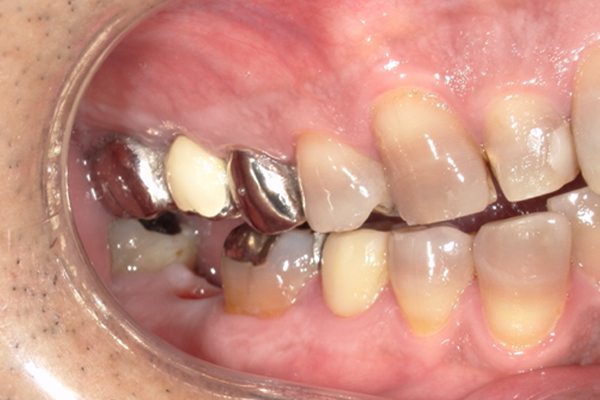

| 主訴 | 奥歯で噛めない、顎が痛い |

|---|---|

| 治療内容 | 奥歯のインプラント治療、前歯・奥歯の被せ物治療 |

| 治療期間 | 6ヶ月 |

| 治療費 | 350万円 |

| 治療リスク | 被せ物をつけた初期の段階で歯がしみることがある(時間とともに改善する) インプラント治療後に3日程度痛みと腫れを伴うことがある |